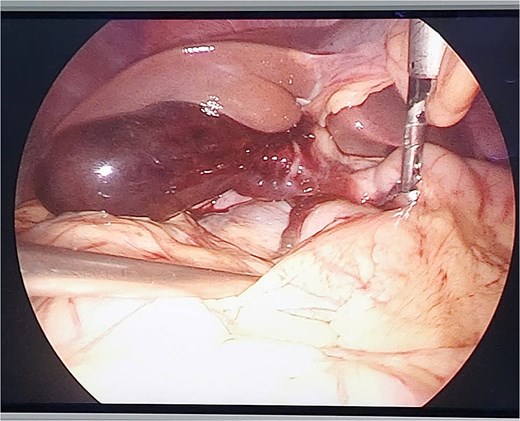

Conversion to open surgery was continuously done to examine the entire duodenum and digestive tract. We explored the omental bursa and then performed Kocher and Cattell-Braasch maneuvers, with any injuries being observed. A cholecystectomy was then performed, followed by cavity lavage with saline, and primary abdominal fascial closure, with abdominal drainage. The patient recovered without complications on the 6 postoperative day and was continuously transferred to The Orthopedic and Trauma Center for broken bone surgery (Fig. 3).